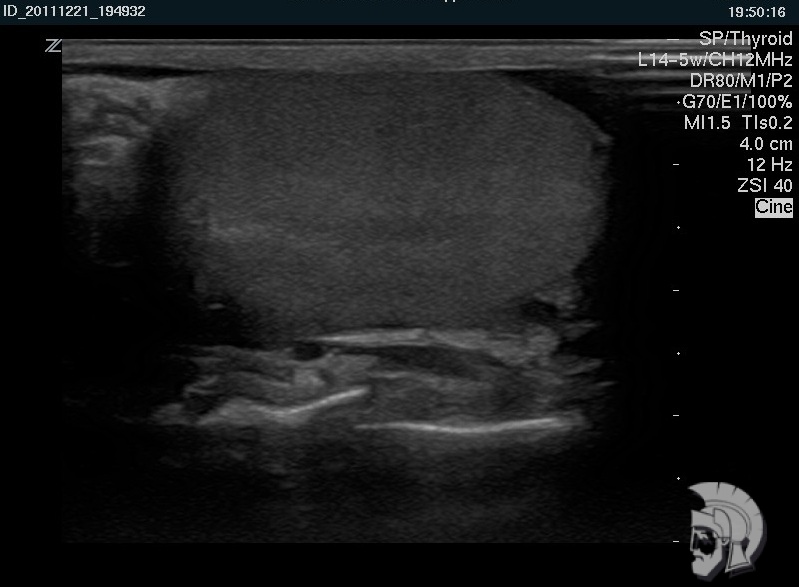

Фото УЗИ мошонки. Нормальная эхо-структура яичка мужчины 22 лет |